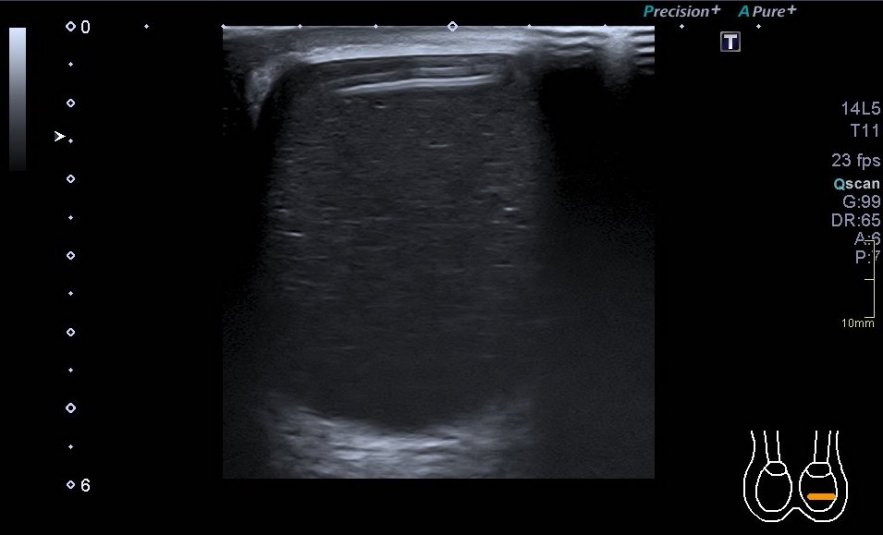

3.Tendón del supraespinoso

En esta parte del estudio te muestro un corte que a mi me parece vital, es el corte en eje largo del supraespinoso y la continuación hacia distal de la bursa apoyada en la cara anterior del húmero. Es una imagen preciosa en normalidad, y es maravillosa cuando nos muestra la bursa llena de líquido. Indicación de que el supraespinoso podría estar roto. Nunca dejes de realizar este corte, es muy importante y vas a encontrar patología en la Bursa en muchas ocasiones.